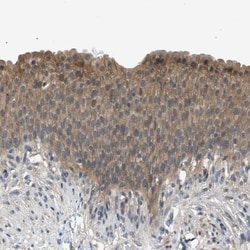

- A53T Mutant Protein-Electron Microscopy-NBP3-14767-img0003.jpg-250.jpg)